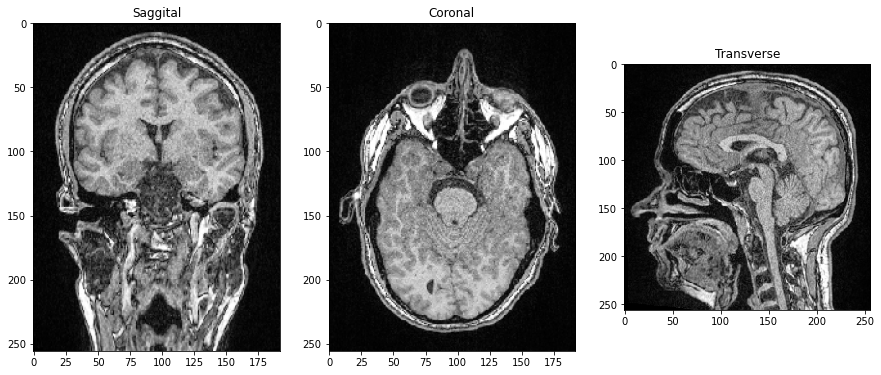

由于所有三个维度都是空间维度,我们还可以制作垂直于图像平面的切片,对应于解剖平面。为了正确定向图像,我们可以通过在末尾添加.T来转置它们的轴。

saggital = image_stack[:,:,128].T

coronal = image_stack[:,128,:].T

transverse = image_stack[96]

fig, axs = plt.subplots(1, 3, figsize=(15,15))

# show orthogonal planes

axs[0].imshow(saggital, cmap='Greys_r')

axs[0].set_title('矢状面')

axs[1].imshow(coronal, cmap='Greys_r')

axs[1].set_title('冠状面')

axs[2].imshow(transverse, cmap='Greys_r')

axs[2].set_title('横断面');